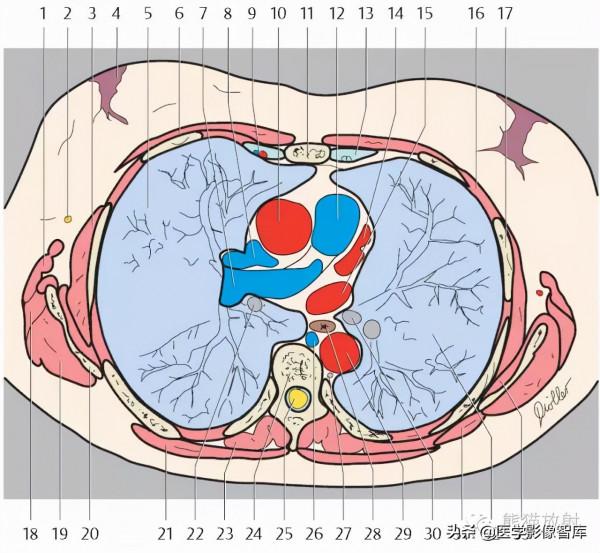

胸部

第八層:肺動脈幹水平

1. Latissimus dorsi muscle 背闊肌

2. Long thoracic nerve 胸長神經

3. Serratus anterior muscle 前鋸肌

4. Glandular tissue of the breast and nipple 乳腺腺體及乳頭

5. Right lung 右肺

6. Pectoralis major muscle 胸大肌

7. Right pulmonary artery 右肺動脈

8. Superior vena cava 上腔靜脈

9. Internal thoracic artery and vein 胸內動脈、靜脈

10. Ascending aorta 升主動脈

11. Sternum 胸骨

12. Pulmonary trunk 肺動脈幹

13. Rib (costal cartilage) 肋骨(肋軟骨)

14. Left pulmonary vein 左肺靜脈

15. Left atrium 左心房

16. Intercostal muscle 肋間肌

17. Rib 肋骨

18. Teres major muscle 大圓肌

19. Infraspinatus muscle 岡下肌

20. Scapula 肩胛骨

21. Trapezius muscle 斜方肌

22. Right inferior lobar bronchus 右肺下葉支氣管

23. Erector spinae muscle 豎脊肌

24. Thoracic vertebra 胸椎

25. Spinal cord 脊髓

26. Azygos vein 奇靜脈

27. Thoracic duct 胸導管

28. Esophagus 食管

29. Descending aorta 降主動脈

30. Left inferior lobar bronchus 左肺下葉支氣管

31. Rhomboid muscle major 菱形肌

32. Left lung 左肺

33. Subscapularis muscle 肩胛下肌